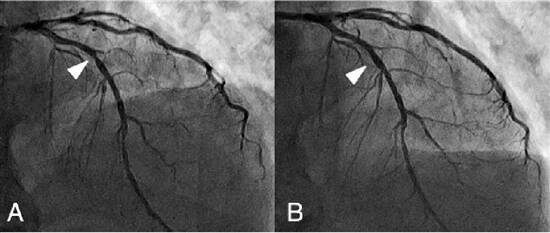

冠状动脉支架植入前后对比